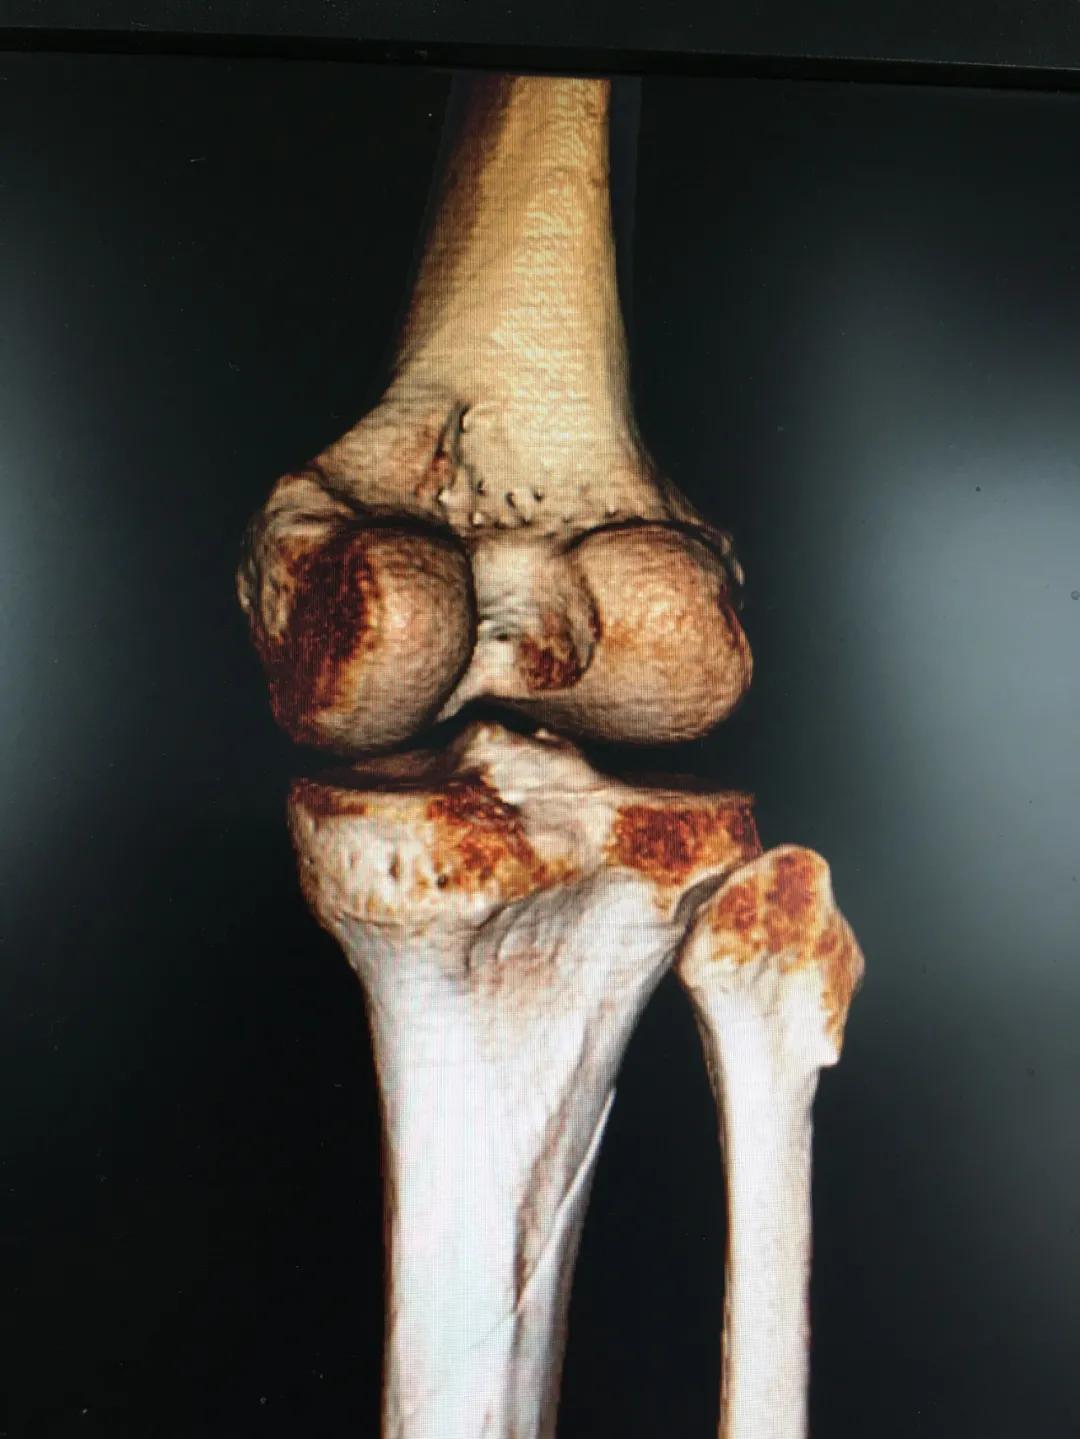

刘阿姨半个月前骑电动车时与小轿车相撞,导致了左胫腓骨粉碎性骨折,小腿骨碎成了三段。"然而,在术前丈夫周先生对刘阿姨的治疗却拿不定主意。“我妻子身上有多种基础疾病,患高血压15年,糖尿病也有8年多了。这里的诊疗技术,能不能保障手术的安全?手术前,我们家属的心中确实也很忐忑!"由于对我院创伤技术水平不太了解,周先生已经准备要转院治疗。

为患者实施的骨折微创复位固定技术是创伤骨科的特色技术。相较传统手术需要20公分的切口,微创手术只需要3公分左右。闭合复位髓内钉固定技术、经皮插板内固定技术(mippo技术)、闭合复位空心螺钉固定技术等一系列的微创复位固定技术,具有切口小、出血少、创伤小、愈合快、疤痕小等优点,骨折术后并发症明显降低,患者还可以早期负重功能锻炼。